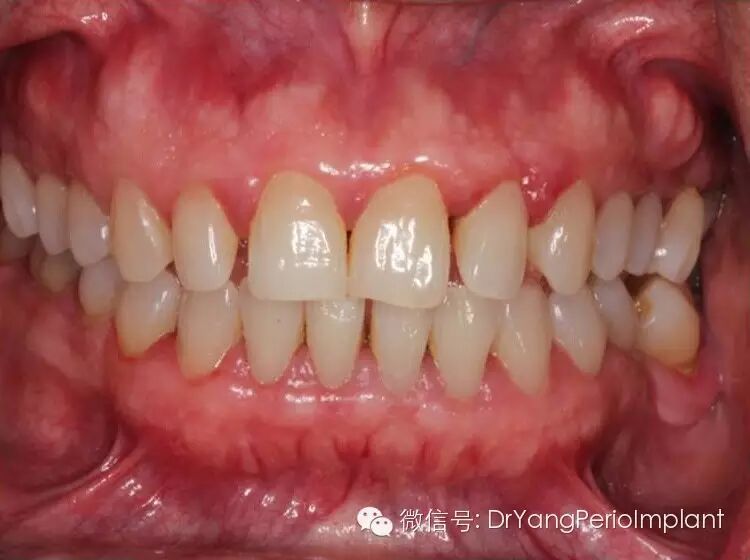

慢性牙周病一例。照片,臨床檢查,X光取自筆者治療過的患者。中年女性,長期沒有正規口腔檢查治療。照片顯示明顯的炎症,臨床檢查顯示附著丟失, X光顯示牙槽骨吸收。